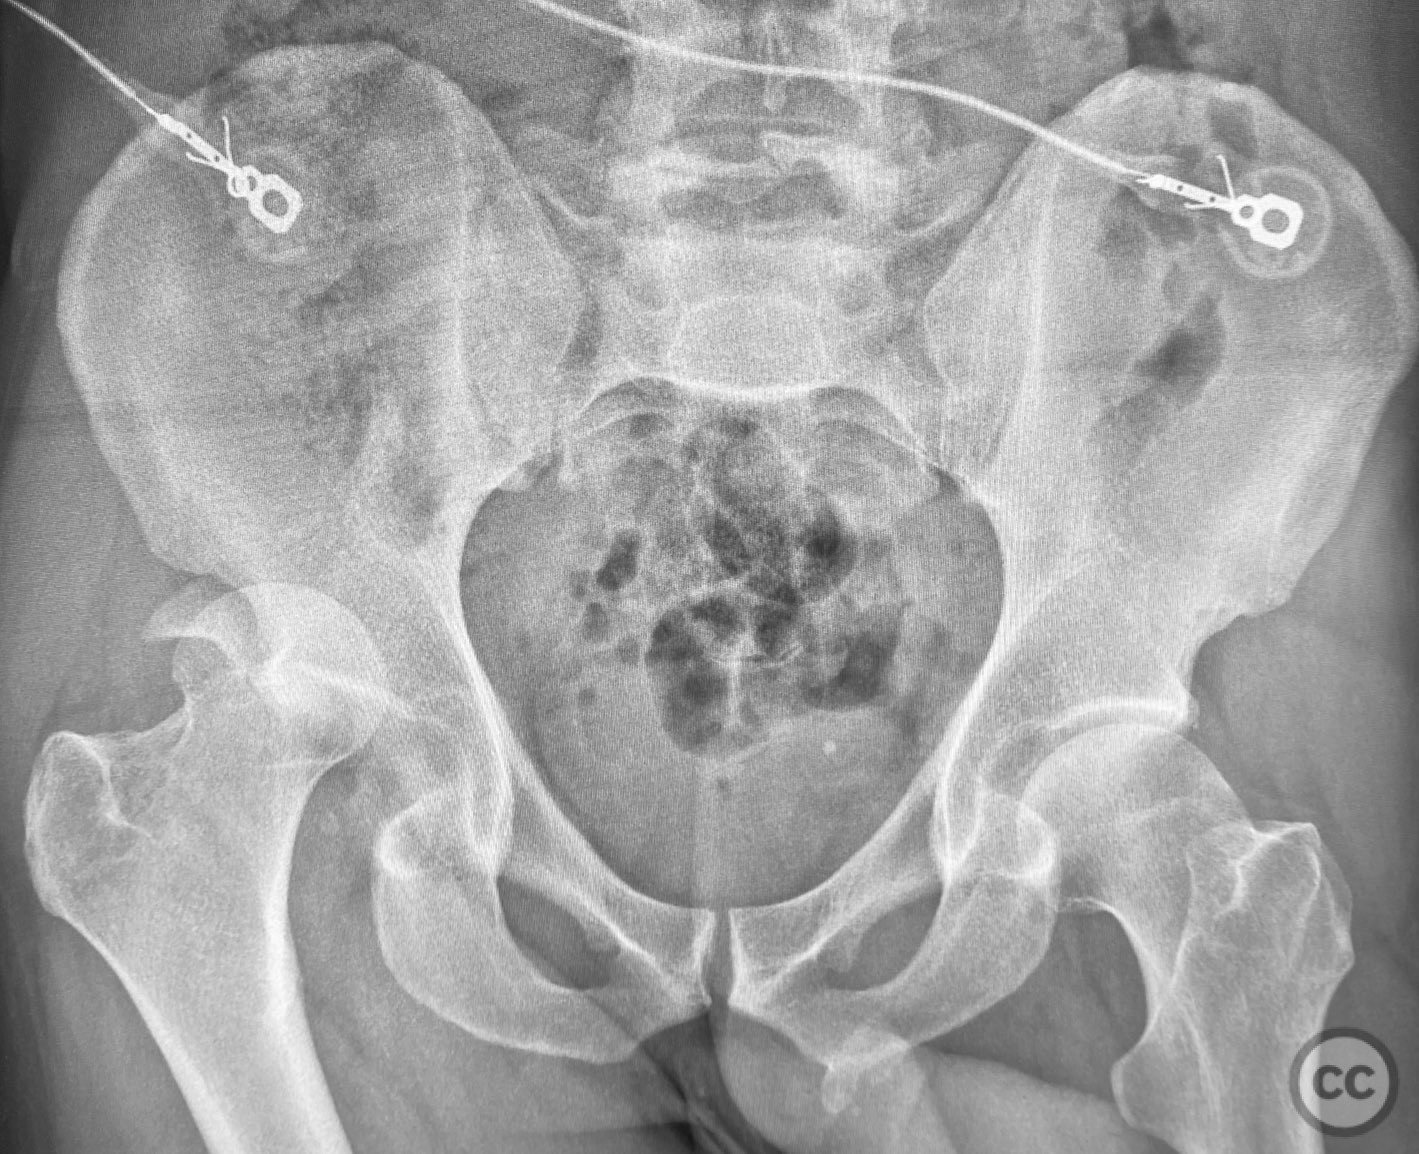

Clinical and radiological findings:  A middle-aged patient sustained a posterior wall acetabular fracture-dislocation, as demonstrated on initial AP pelvic radiograph. The film revealed a sizeable posterior wall fragment, cranial lateral impaction of the acetabular dome, and subtle deformation of the femoral head contour. Neurovascular examination was performed, including assessment of distal pulses and sciatic nerve function. The ipsilateral knee and anterior chest were examined for associated injuries (including possible knee ligamentous injury and thoracic trauma). An initial attempt at closed reduction under sedation was unsuccessful.

Planning remarks:  The preoperative plan included advanced imaging with CT, including 3D surface renderings, to further delineate the extent of articular impaction, wall fragment size, and comminution. The plan was for open reduction and internal fixation via a posterior Kocher-Langenbeck approach in the prone position. Elevation of impacted articular segments was planned, with structural support using autologous bone graft harvested from the greater trochanter. Fragment-specific fixation was planned with a spring hook plate for the cranial wall fragment and a reconstruction plate for the main posterior wall fragment.